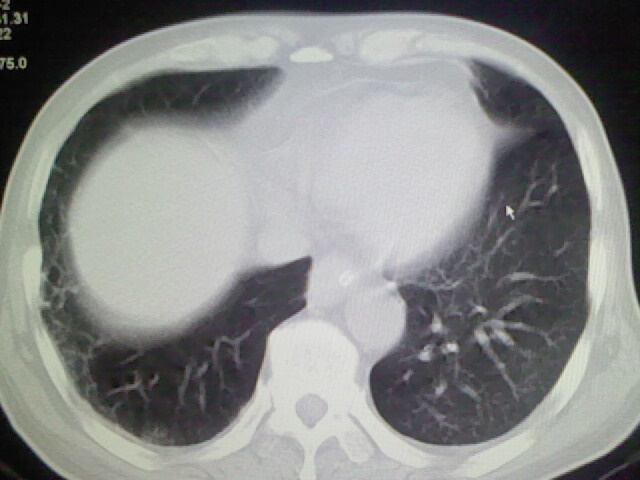

男,70岁,脑出血,长期卧床,左侧背部可触及肿块

右肺病灶考虑炎症性。

右肺病灶考虑炎症性

考虑右肺及左肺下叶炎症。

右肺及左肺下叶炎症。

考虑右肺及左肺下叶慢性炎症。

右侧肺部见片状密度增高影,边缘模糊。考虑炎症。另食管壁增厚。

右肺肺气肿并炎症。

右肺上叶前段病呈楔形,其尖端指向肺门,考虑肺动脉栓塞可能性大.